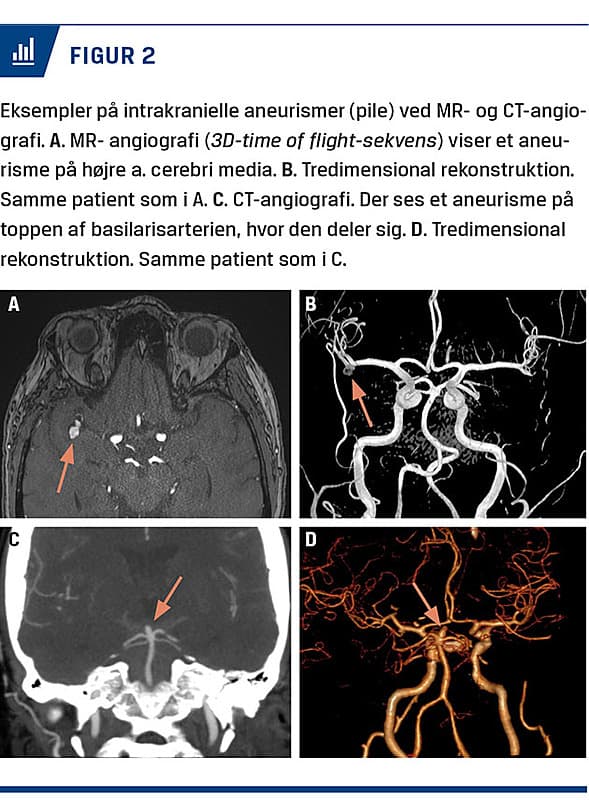

Screening for IA kræver udførelse af en arteriografi. Denne kan udføres noninvasivt som MR-angiografi eller CT-angiografi, der hver har deres styrker og svagheder. Eksempler er vist i Figur 2.

Til MR-angiografi anvendes der ofte 3D-time of flight (TOF)-sekvenser som angiografi sammen med sekvenser til at se hjernens parenkym. Til TOF anvendes der ikke kontrast. MR-angiografien er derfor hverken strålebelastende eller potentielt skadelig for nyrerne. Derfor vil undersøgelsen ofte være god til unge mennesker samt personer med nedsat nyrefunktion. Dog tager undersøgelsen relativt lang tid, og skannerens gantry er snæver, hvilket kan blive et problem ved svær adipositas eller klaustrofobi. Desuden kan metalliske og elektroniske implantater (f.eks. pacemakere) kontraindicere undersøgelsen.

CT-angiografi er en strålebelastende undersøgelse, hvor der anvendes jodholdig kontrast, hvilket forudsætter adækvat nyrefunktion. Da det er en strålebelastende undersøgelse, er den mindre egnet til yngre personer, især hvis man forventer at skulle foretage flere skanninger. Fordelen er til gengæld, at undersøgelsen er hurtigt, og at de fleste kan medvirke til den.